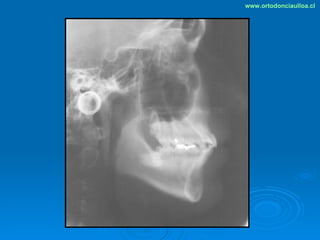

Este documento presenta dos casos clínicos de pacientes que recibieron tratamiento de ortodoncia. El primer caso fue de una paciente femenina de 14 años con apiñamiento dental y mordida cruzada que fue tratada mediante extracción de premolares y alineamiento dental. El segundo caso fue de un paciente masculino de 14 años con clase II esqueletal y desarmonía dentomaxilar que fue tratado con extracción de premolares y corrección de mordida. Ambos casos mostraron mejoría después de 3 años de tratamiento.